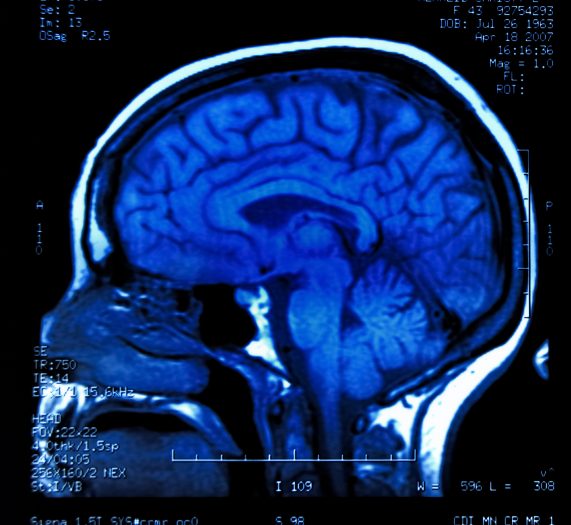

magnetic resonance image (MRI) of the brain

نوروسافاری| محققان دریافتند فقر در کنار آسیب‌های روزانه‌ای که به کودکان وارد می‌کند، به طور ویژه‌ای می‌تواند آسیب‌های زیادی به مغز کودکان وارد آورده و در تغییر ساختار مغزی کودکان مؤثر باشد.

اما چه قسمتی از مغز کودکان بیشتر از فقر تأثیر می‌پذیرد؟ به عقیده محققان هیپوکامپ (ناحیه‌ای از مغز که مسؤول یادگیری و احساسات است) به‌ شدت از فقر و رنج‌هایی که مادر و کودک در زندگی متحمل می‌شوند، تأثیر می‌پذیرد.